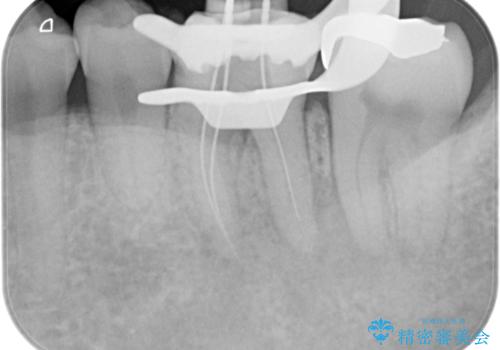

根管治療から被せ物の治療

- 噛んだ時の痛みを主訴に当院受診されました。

根管治療を行なったのち、症状改善を認めオールセラミッククラウンにて修復治療を行なっております。

┌7は今回の治療後打診(-)、正常歯髄へ診断のもと経過観察を行なっております。